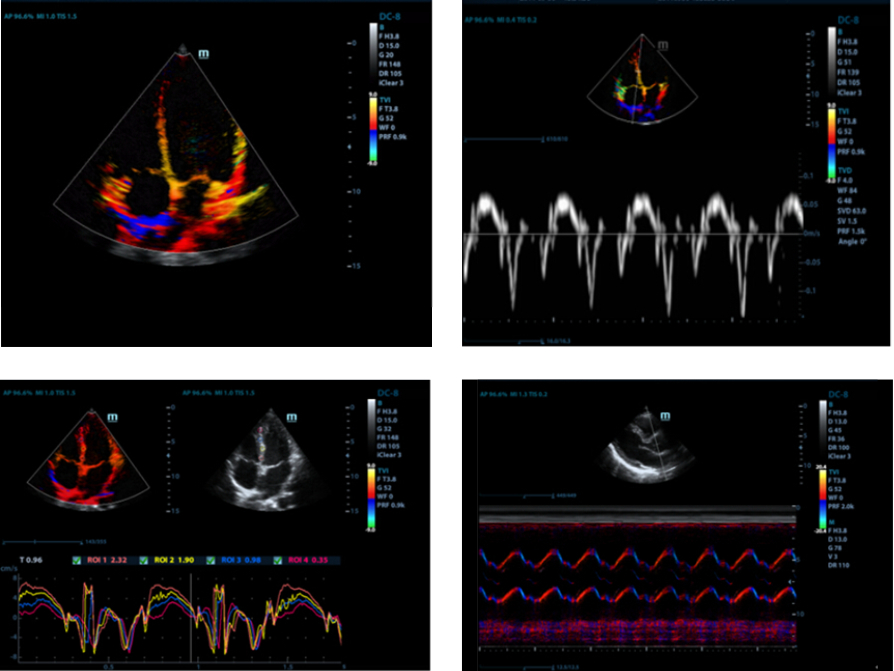

Free Xros M?

Osservazione anatomica precisa posizionando liberamente le linee campione su ciascun angolo. Migliori immagini con visualizzazione simultanea fino a 3 linee campione.

Free Xros CM?

Esatta valutazione del movimento miocardico in diverse fasi, con la possibilit├Ā di determinare allo stesso tempo la sincronizzazione miocardica. Alta frequenza di fotogrammi a garanzia di risultati precisissimi:

TDI

Le immagini doppler tissutali consentono di valutare quantitativamente il movimento e la funzione miocardica a livello locale, assicurando modalit├Ā TDI complete per diagnosi pi├╣ rapide e dirette.